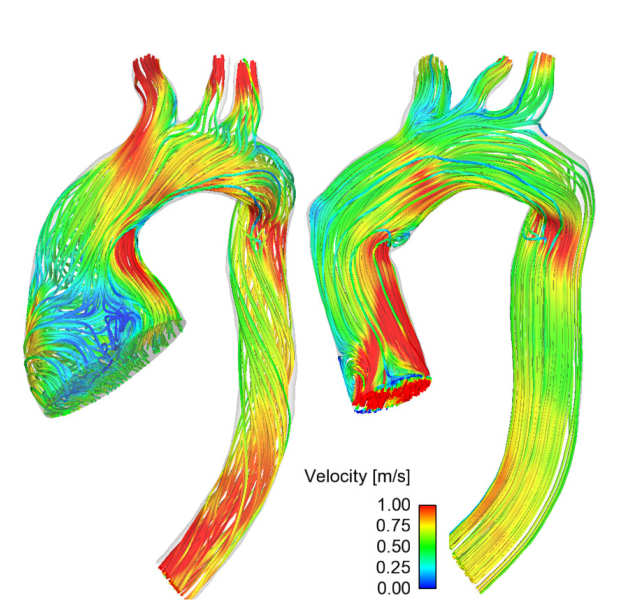

4D Flow

We are using 4D flow MRI to examine the relationship between aortic blood flow patterns, wall shear stress and the severity of aortic wall degradation in patients with ascending aortic aneurysms (AsAA). We aim to develop a rupture prediction model for patients with AsAA’s. using the phase-contrast MRI and biomechanical data.

We are using 4D flow MRI to examine the relationship between aortic blood flow patterns, wall shear stress and the severity of aortic wall degradation in patients with ascending aortic aneurysms (AsAA). We aim to develop a rupture prediction model for patients with AsAA’s. using the phase-contrast MRI and biomechanical data.